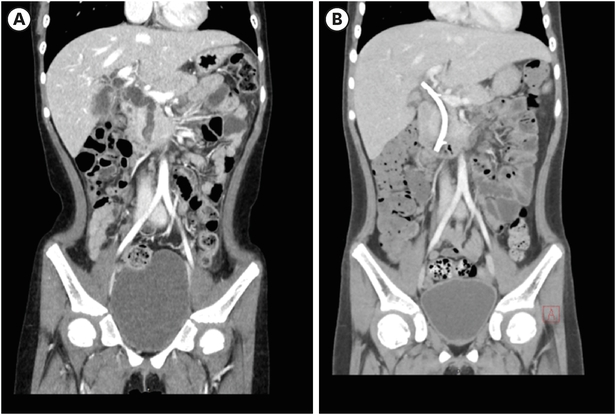

A 7-year-old girl visited the pediatric department of Asan Medical Center for endoscopic retrograde cholangiopancreatography (ERCP) to remove a distal common bile duct (CBD) stone. She was previously healthy and visited a nearby hospital due to abdominal pain and vomiting lasting for 13 days, and jaundice progressed the day before hospital visit. Computed tomography (CT) revealed tortuous dilatation of the extrahepatic bile duct abruptly narrowed in the distal CBD level with several distal CBD stones and anomalous pancreaticobiliary ductal union (APBDU, P-C type). The common channel was measured as 1.9 cm in length. These findings suggested type I CC related to APBDU. Secondary cholecystitis, cholangitis, and pancreatitis were additionally found (Fig. 1A). The same findings were confirmed on magnetic resonance imaging (Fig. 1B). After failure of the first ERCP at the previous hospital, she kept non per oral for one week, but symptoms and lab findings were never relieved (Table 1). So, she was determined to transfer to Asan Medical Center. ERCP was performed. Both pancreatic and CBD were successfully cannulated, and a 10 Fr. Endoscopic retrograde biliary drainage stent was retained in the bile duct for remnant stone excretion. No residual stone was found in follow-up CT in 3 days post ERCP (Fig. 2). Serum levels of liver enzymes, bilirubin, and amylase/lipase decreased to the normal range. Two months later, robotic CC excision and Roux-en-Y hepaticojejunostomy were performed. Severe adhesion and fibrosis around the CC reflecting chronic inflammation were noted. Type I CC was identified, and CBD was resected proximally above the cystic duct and distally at the upper border of the pancreas head. The patient recovered without acute complications. In ultrasonography of post-operative day (POD) 7, no abnormal finding was observed except a small fluid collection around hepaticojejunostomy. She was discharged on POD 9. In the permanent biopsy, edematous mucosal change of gallbladder (GB) and cystic duct was observed, but the diameter of the cystic duct was within the normal range (0.4 cm). In microscopic findings, papillary hyperplasia was identified. The resected CC was 2 cm in length and 2 cm in the widest circumference. It was pathologically confirmed as a CC, accompanying fibrosis and wall thickening changes of CBD, and low-grade BilIN was identified from the resected CC (Figs. 3 and 4). Papillary hyperplasia in GB suggests chronic inflammation in the biliary system due to CC such as BilIN. There was no involvement in the cystic duct and GB as in Type VI.

Fig. 1

CT and MRCP at initial diagnosis. (A) Contrast-enhance CT was performed, and it revealed severe dilatation of extrahepatic bile duct with wall thickening and narrowing in the distal CBD level. Also, mild dilatation of both proximal intrahepatic bile ducts were observed. Several distal CBD stones were found. (B) In MRCP, anomalous pancreaticobiliary ductal union (1.9 cm in length, C-P type) was observed.

CT, computed tomography; MRCP, magnetic resonance cholangiopancreatography; CBD, common bile duct.